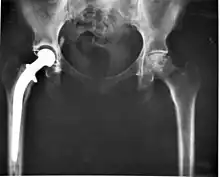

- Knæ og hoftealloplastik – Indsættelse af et kunstigt led